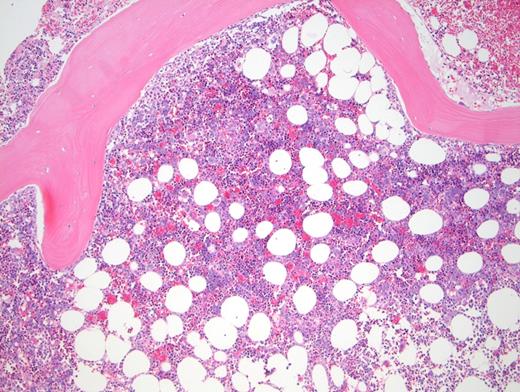

Peripheral blood showed abnormal red cell findings (Figure 1) with erythroblastosis (not shown). Aspirate showed trilineage hematopoiesis with erythroid predominance (Figure 2). Core biopsy showed hypercellular marrow (Figures 3 and 4) with focal areas of marrow damage (Figure 5). Hemoglobin high-performance liquid chromatography (HPLC) was performed (Figure 6).

The peripheral blood showed numerous target cells, burr cells, and microcytes, as well as partially sickled cells and blister-like cells. Core biopsy shows erythroid hyperplasia with large clusters of sickled cells (present in macrophages by CD68 stain; not shown).